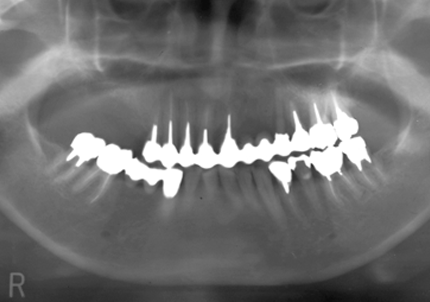

1.初診時口腔内(2007年6月30日)

2.右側上顎洞サイナスリフト後にインプラント埋入

↑ サイナスリフト術前

↑ サイナスリフト術後

3.右上インプラント補綴物装着(2009年7月24日)

↑ 右上サイナスリフト後にインプラント埋入

4.左上下7番インプラント補綴物装着(2010年5月24日)

5.右上7番インプラント(2013年11月6日)

6.右下6,7番インプラント(2017年9月15日)

7.左上6番インプラント(2021年2月21日)

8.初診より現在に至る

強い歯ぎしり、くいしばりで奥歯の歯牙破折、深い虫歯で保存不可能となり全顎治療となる。

↑ 2007年6月30日(初診)

↑ 2025年9月9日

治療後は経過良好